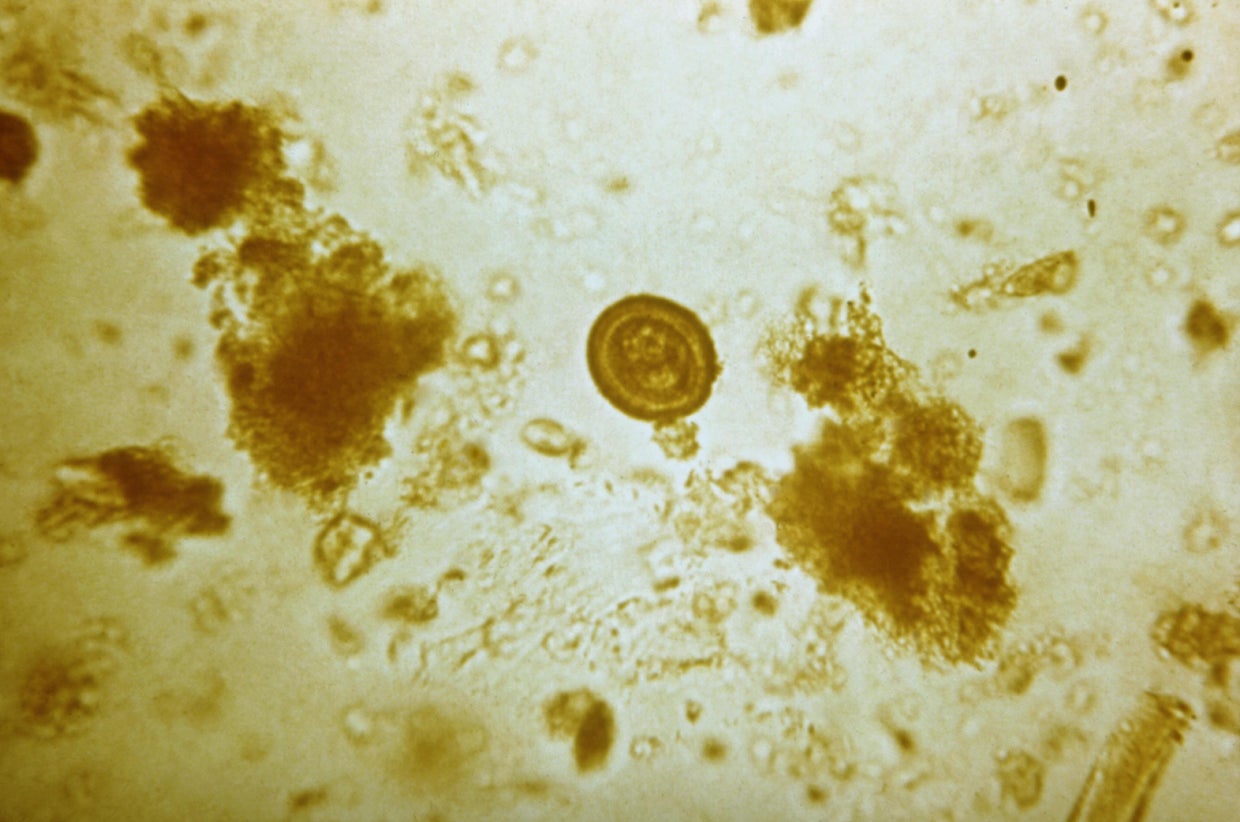

46. Larval tapeworm infection

CDC via Getty Images

Mortality rate: 2.2%

Cysticercosis is a parasitic tissue infection caused by tapeworm larvae. The disease is spread through contact with waste from an infected person.